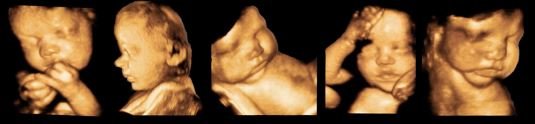

Baby Belly Pregnancy Spa & Imaging Center

#6

$$

★★★★

(5 reviews)

Diagnostic ImagingDay Spas

201 Ruccio Way